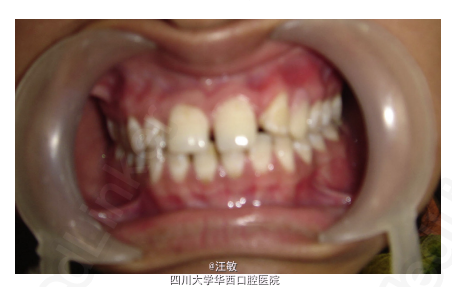

患者因上前牙美观问题就诊。

检查发现22牙缺失,23牙处于22牙位置,左上乳尖牙滞留。所有的咬合关系都正常。